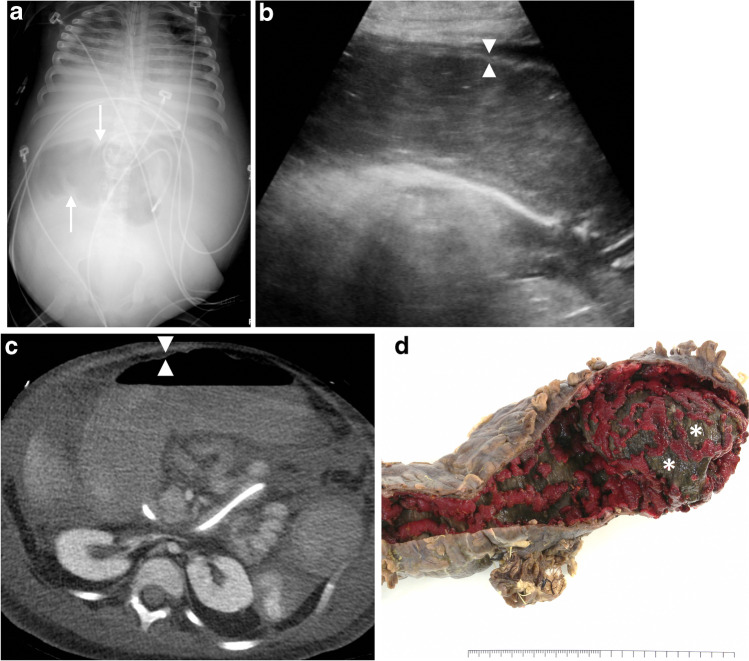

Toxic megacolon is an uncommon fulminant transmural colitis that most frequently complicates pseudomembranous and ulcerative colitis. Inflammation and necrosis of smooth muscle in the muscularis propria, along with damage to the myenteric plexus (a component of the enteric nervous system sandwiched between the two layers of muscularis propria smooth muscle), lead to nonobstructive colonic dilation [26]. Colonic dilation and abnormal fold pattern on radiographs along with clinical severity generally dictate management; however, US can be an expeditious portable adjunct in clinically tenuous patients. The diagnosis is suggested on US by the combination of luminal dilation greater than 6 cm (often most marked in the transverse colon) and bowel wall thinning less than 2 mm, with associated loss of haustration (Fig. 8) [27]. Management involves initial treatment of the underlying medical condition. If medical treatment fails, early colectomy prior to colonic perforation should be performed because perforation greatly increases morbidity and mortality [28]. Because subtle free air can be difficult to detect on US, images should be interpreted in conjunction with radiography and with a low threshold for obtaining further cross-sectional imaging.

Fig. 8.

Toxic megacolon. a Abdominal radiograph in a 6-year-old girl with C. difficile colitis complicated by toxic megacolon and abdominal compartment syndrome shows a nonspecific abnormal gas pattern with dilation of the transverse colon and haustral blunting (arrows). b Sagittal gray-scale US of the descending colon in the same girl demonstrates luminal dilation and complete loss of haustration, as well as diffuse thinning (<2 mm) of the bowel wall with loss of the normal laminar architecture (arrowheads), a late finding. c Immediately subsequent axial contrast-enhanced CT image shows pan-colonic involvement with mural thinning and diminished enhancement, indicating ischemia (arrowheads). The girl required total colectomy. d Gross specimen photo from a different child, an 11-year-old boy, with toxic megacolon complicating ulcerative colitis shows a dilated colon with a denuded and thinned wall characterized by loss of mucosa and submucosa down to the muscularis propria (brown, asterisks) and patchy areas of residual mucosa (red)